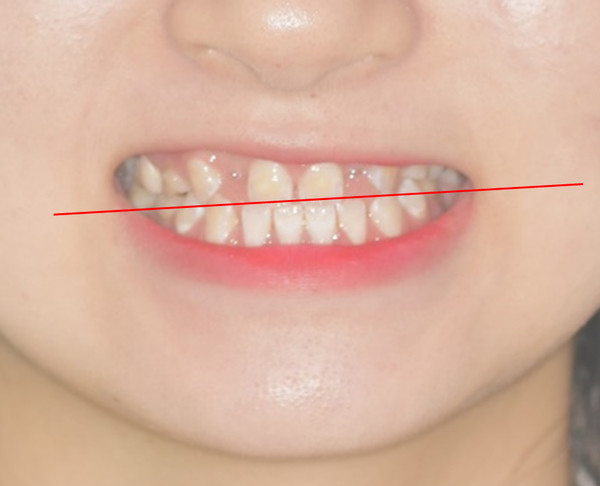

상악 양측 견치의 수직적 위치가 다른 것을 알 수 있습니다. 이는 추후 교정치료가마무리되면 전치부 교합평면의 canting이 확연히 보이게 되므로 문제가 될 수 있습니다.

반대교합 수정과 측절치 임플란트 식립및 temporary crown을 이용한 보철수복이 이루어졌습니다. 양측 견치의 수직적 차이가 조금 더 명확해졌습니다.

Occlusal canting을 수정하기 위해 상악 좌측 임플란트보철물에 bracket을 기울여 붙여서 slot의 방향대로 archwire가 삽입되었을때 좌측 견치는 정출되고 우측 견치는 함입되도록 하였습니다.

Slot의 방향에 맞춰 전치부 occlusalcanting이 개선되었습니다. 좌측견치의 정출이확연히 눈에 띕니다.

초진시부터 마무리까지 양측 견치 tip을 연결한 선을 기준으로 frontal occlusalplane의 변화를 비교 시occlusal canting의 개선을 확인할 수 있습니다.